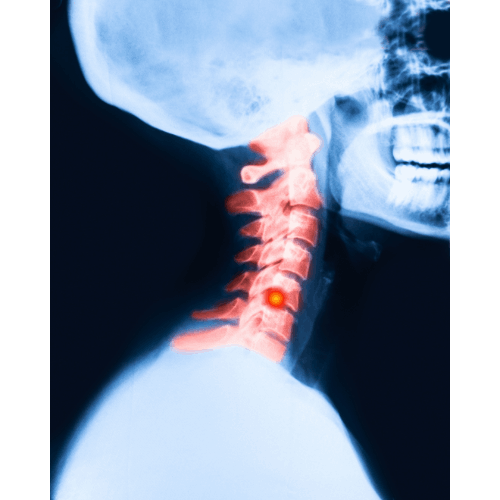

The cervical spine, a marvel of flexibility and support, consists of seven vertebrae, with the C5-C6 segment being particularly noteworthy.

This segment, located in the lower part of the neck, plays a pivotal role in supporting the head and enabling a wide range of motion.

The C5-C6 disc, sandwiched between the fifth and sixth cervical vertebrae, is responsible for cushioning these bones and facilitating movement.

When this disc herniates, it means the inner gel-like substance breaks through its tougher exterior, potentially causing nerve irritation or compression.

Diagnosing a C5-C6 herniated disc usually involves a combination of physical examinations, where doctors check for pain distribution and nerve function, and imaging tests like MRI or CT scans, which provide a detailed look at the spinal structures.